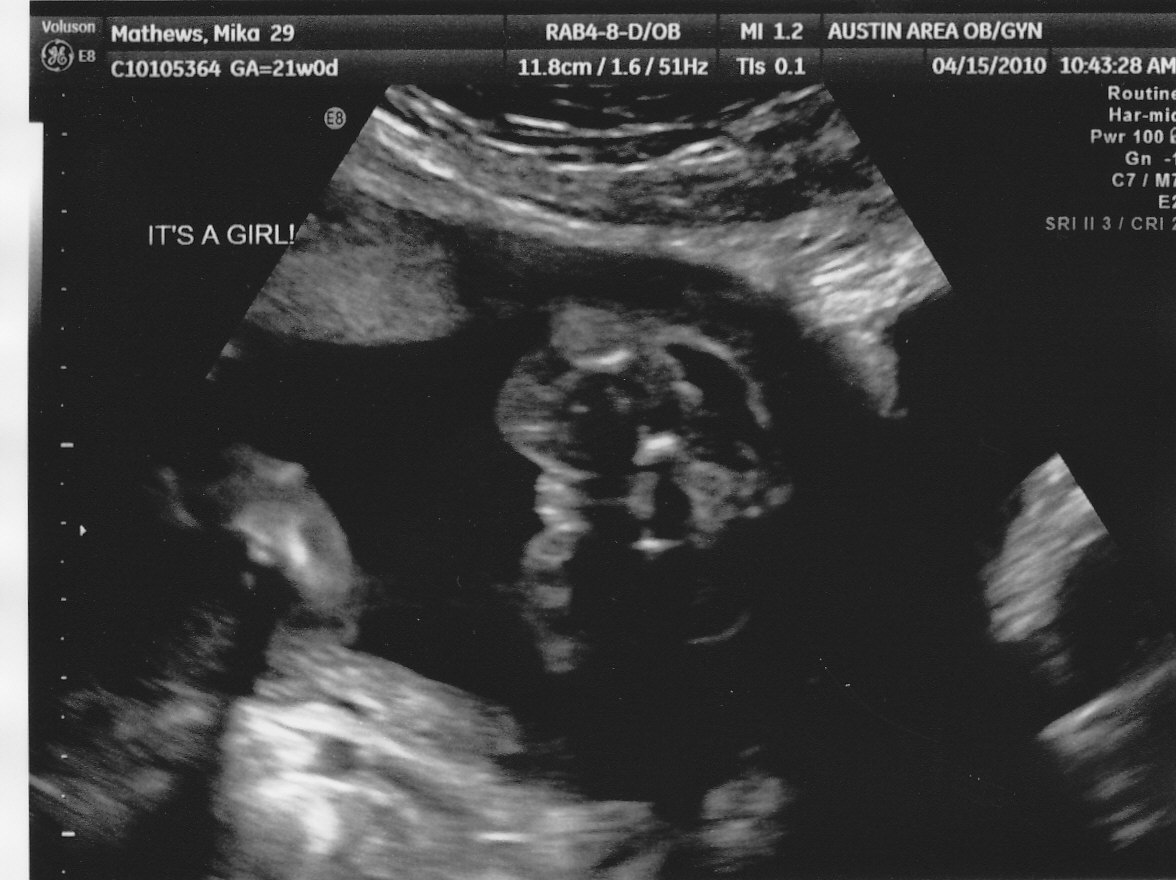

...It's definitely a girl!!! We had a sonogram today (the big one). They did all the measuring and weights. She weighs 14 oz. and her measurements average her out to be 21 weeks 1 day. She's perfect. No health issues, no alarms. God is good.

The sonogram was partly done is 3D, but every time the sonographer tried to get a picture of her face, she put both her feet in the way. It's actually pretty cute (she's laying in there, folded in half).